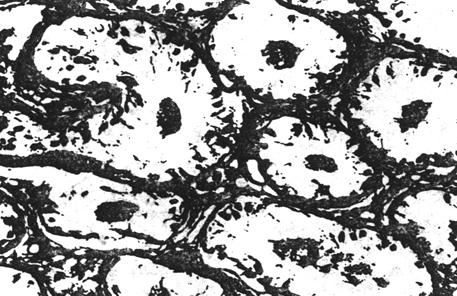

①正常睾丸组织:正常睾丸的曲细精管内可见正在进行分化的各级生精细脆,约5~6层,排列紧凑,规则,以基层膜列管腔依次是精原细胞,初级精母细胞,次级精母细胞,精子细胞和精子。此外还有支持细胞,其体积较大,胞体以基底膜一直伸到管腔。曲细精管之间是间质内有成堆的间质细胞。

图8-3-3 正常人睾丸活检图象